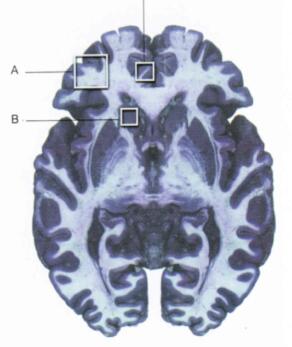

U osób z OCD pobudzenia zaczynając się od jądra ogoniastego (A), które wyzwala uczucie przymusu działania, przez oczołodołowej okolicę kory przedczołowej (B) stwarzającą uczucie, że coś jest nie tak, i korę zakrętu obręczy, zwracającą uwagę na uczucie zakłopotania. |